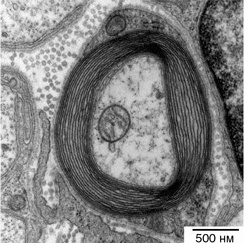

Иллюстрация к книге — Искра жизни. Электричество в теле человека [i_008.jpg]

Миелинизированный нерв. Видны слои изолирующего миелина, намотанные на аксон. Небольшой органоид в центре нерва – это митохондрия, один из генераторов энергии клетки.

Многочисленные шванновские клетки расположены вереницей вдоль всей длины аксона. Через каждые несколько микрометров между соседними шванновскими клетками образуется небольшой зазор, называемый перехватом Ранвье, который позволяет оголенной мембране нерва контактировать с внеклеточной жидкостью. Поскольку миелиновая оболочка является хорошим изолятором, электрический ток может течь от нервной клетки к внеклеточной жидкости только в местах перехватов. Перехваты, таким образом, служат ретрансляционными станциями, усиливающими потенциал действия и повышающими его скорость. Фактически нервный импульс движется быстрее в миелинизированных нервах потому, что его передний фронт перепрыгивает последовательно от перехвата к перехвату. Это объясняет, почему миелинизированные нервы передают потенциалы действия намного быстрее немиелинизированных нервных волокон.